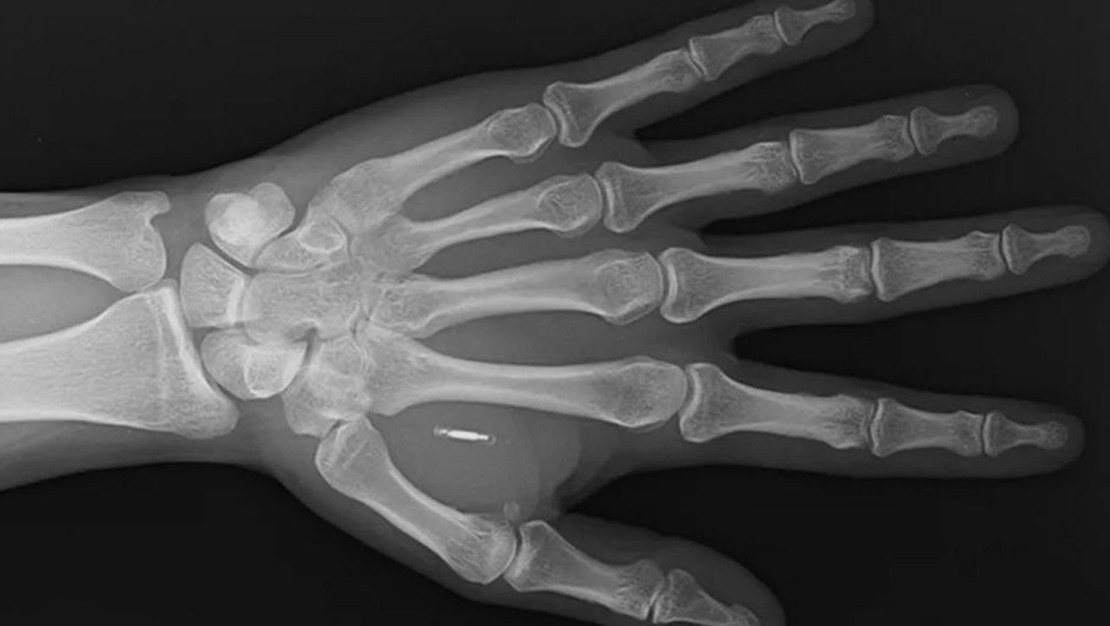

ABD’nin Missouri eyaletinde ikamet eden bir sihirbaz ve moleküler biyolog, yaratıcı bir fikirle eline mikroçip yerleştirdi. Ancak, işler planladığı gibi gitmedi; çünkü şifresini unuttu. “Zi the Mentalist” sahne adıyla bilinen Zi Teng Wang, sosyal medya platformu üzerinden durumunu takipçileri ile paylaştı ve başparmağı ile işaret parmağı arasındaki etin içinde bulunan mikroçipi gösteren röntgen görüntüsünü de ekledi. Wang, “Şu anda kendi bedenimin içindeki teknolojiye erişemediğim, tamamen kendi hatamdan kaynaklanan küçük bir siberpunk distopyası yaşıyorum” şeklinde yazdı. Wang’ın durumu, vücuda yerleştirilen teknolojilerin unuttukları şifreler gibi detaylar nedeniyle getirdiği risklerin altını çiziyor; zira bir şirket kapanabilir veya bir ürün sonlandırılabilir.

Wang, Facebook paylaşımında bu RFID (Radyo Frekansı Tanımlama) çipini yıllar önce çeşitli sihir numaralarında kullanmak için eline yerleştirdiğini ifade etti. Ancak izleyicilerin telefonlarını eline yaklaştırmaları bu sihir numaralarının beklediği gibi gizemli görünmesini sağlamadı. Wang, “Birinin telefonundaki RFID okuyucunun nerede olduğunu bulmaya çalışarak elime tekrar tekrar telefon bastırmaları, düşündüğüm kadar büyüleyici ve etkileyici olmadı” diye ekledi. Ayrıca birçok izleyicinin RFID okuyucuları devre dışıydı, kendi telefonunu kullanmak ise numaranın büyüsünü tamamen yok ediyordu. Sihirbazlık alanından uzaklaşan Wang, çipi daha sonra bir Bitcoin adresine yeniden yönlendirdi fakat birkaç yıl sonra link çökünce sorun baş gösterdi. Şifreyi hatırlamadığı için çipine erişemediktir.